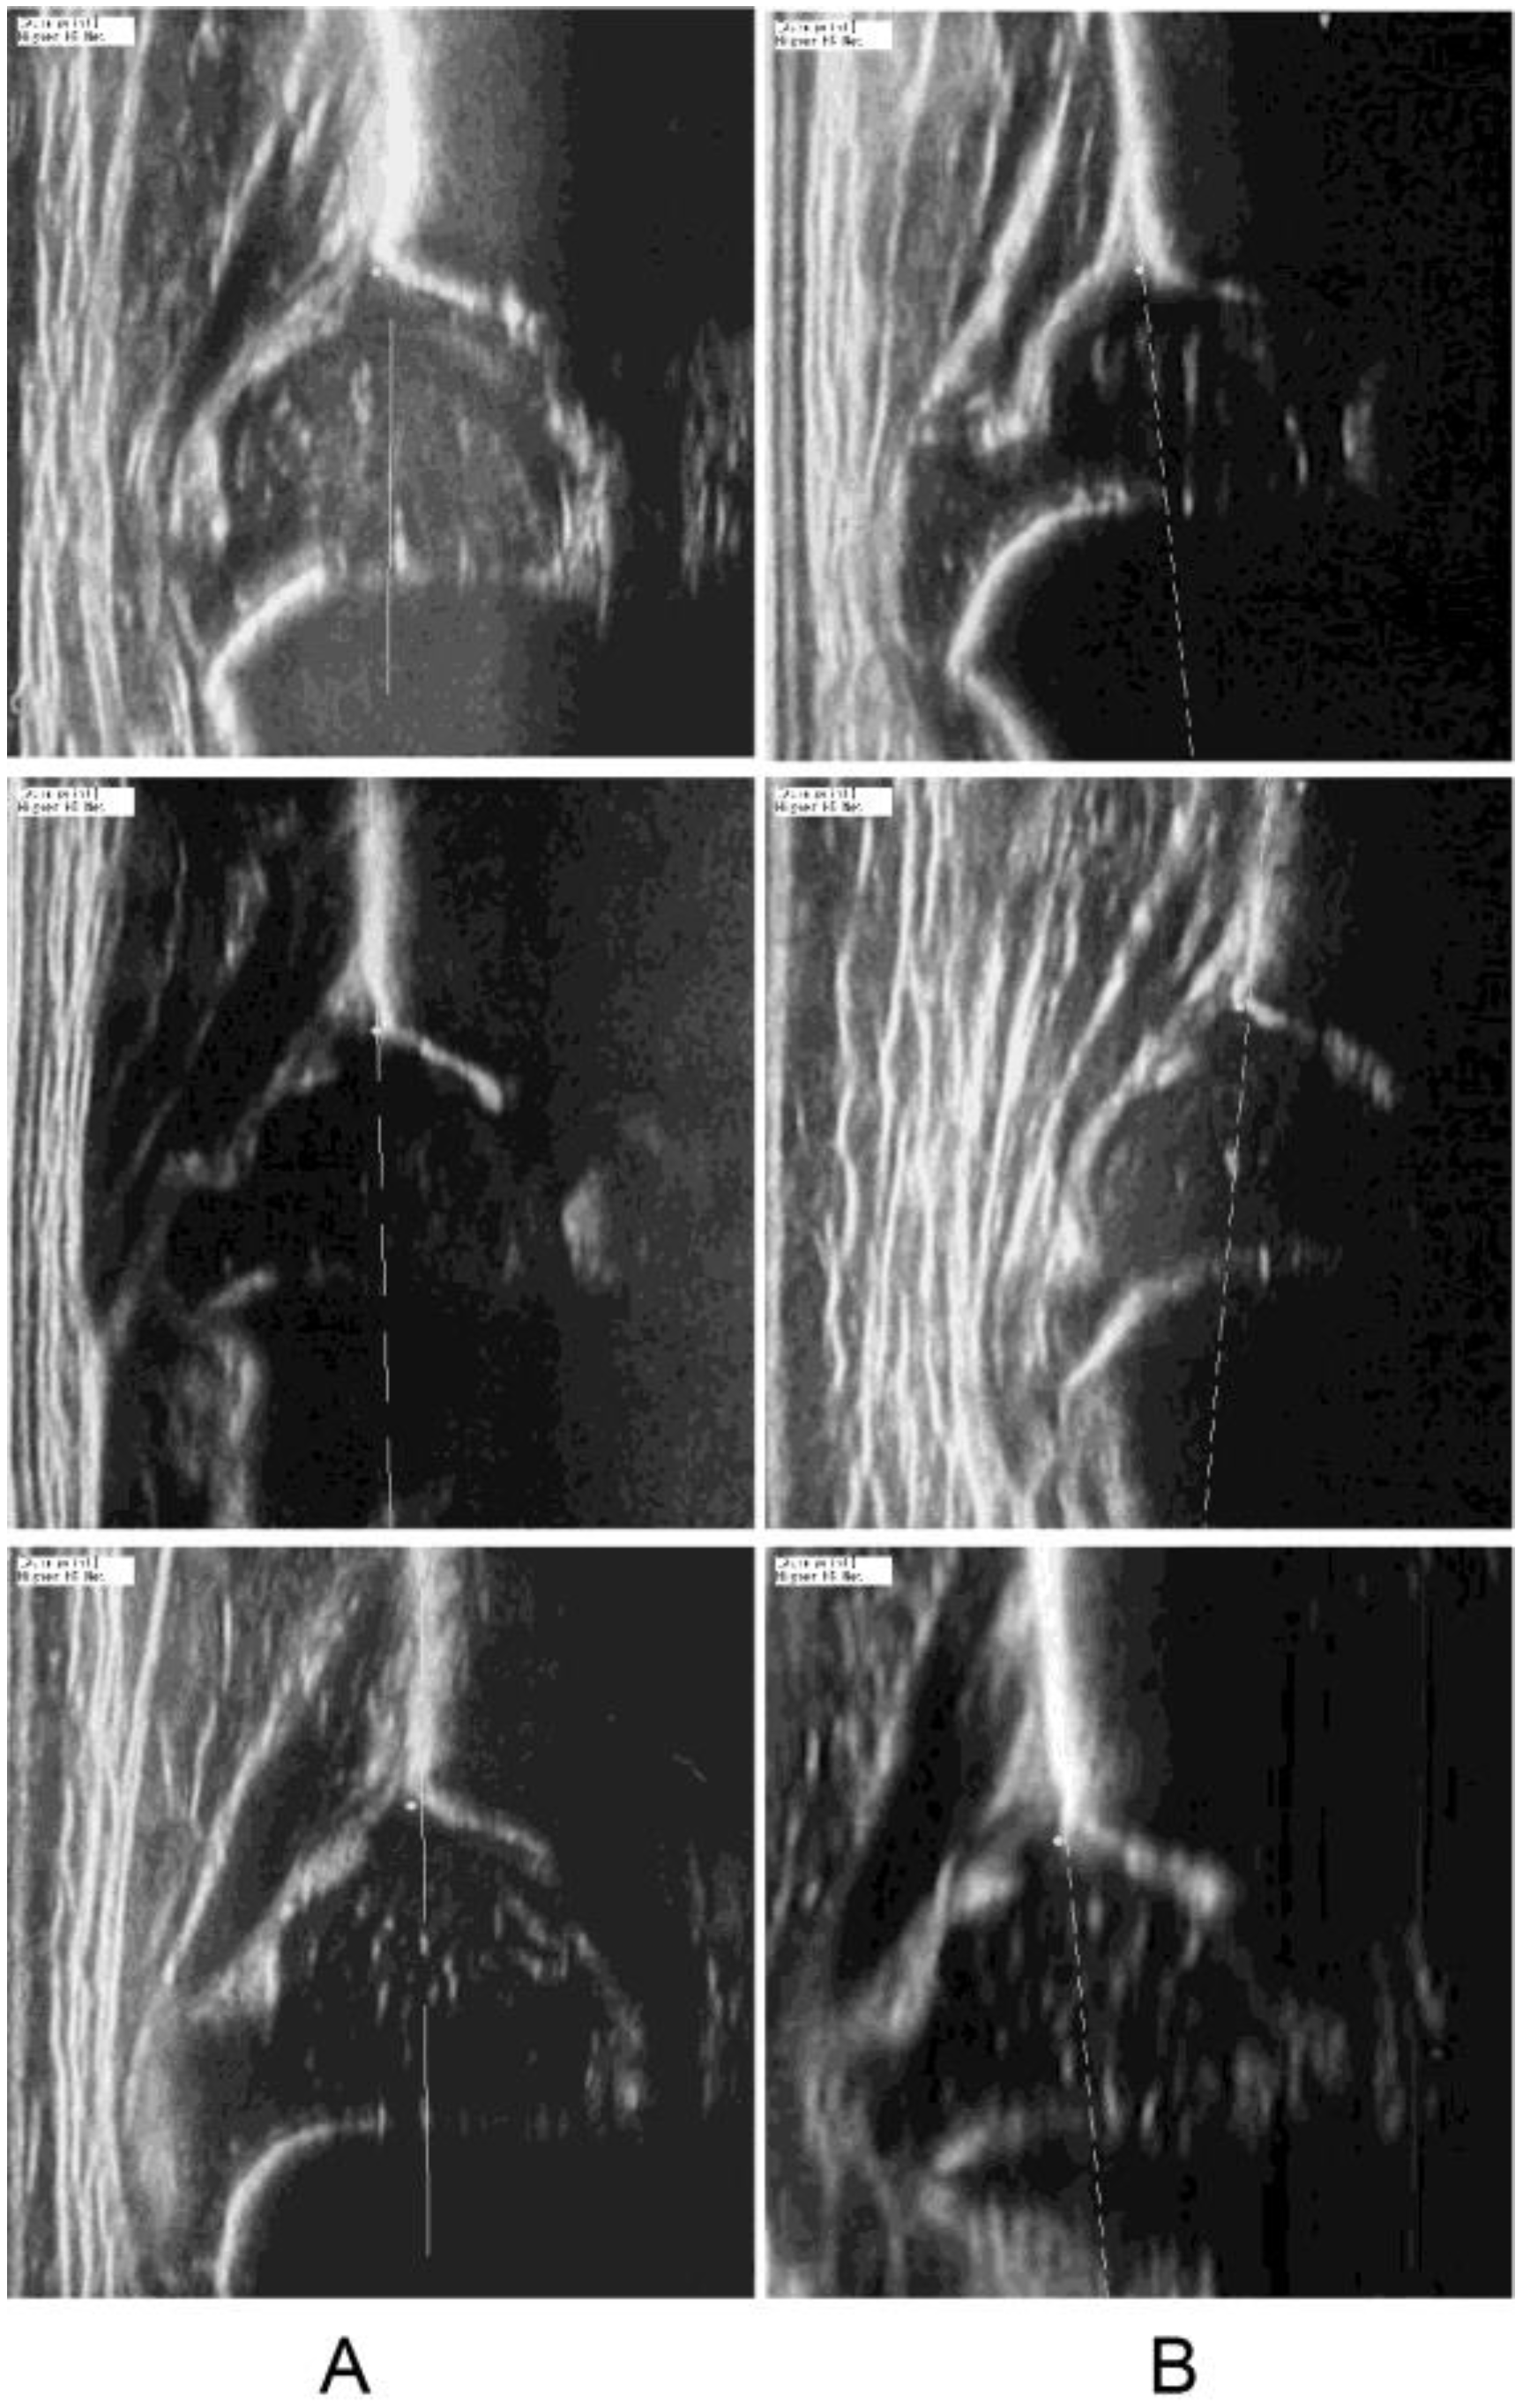

2.3.2. Quality Assessment Through Signal Heterogeneity Analysis

3.3. Step 3: Accuracy of Detecting DDH in Qualified Images